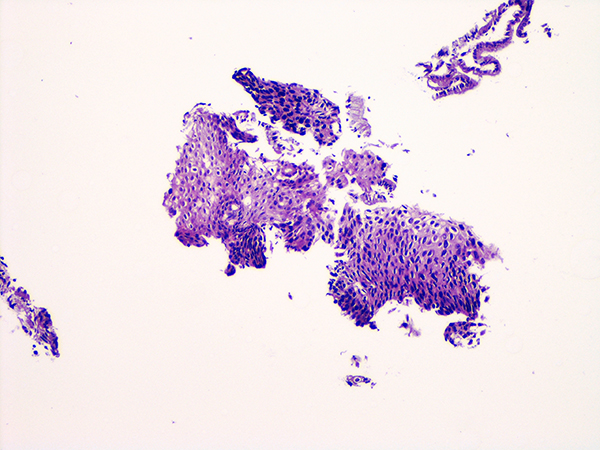

Case 1

Soft Bx CIN 2 10x - Low Power